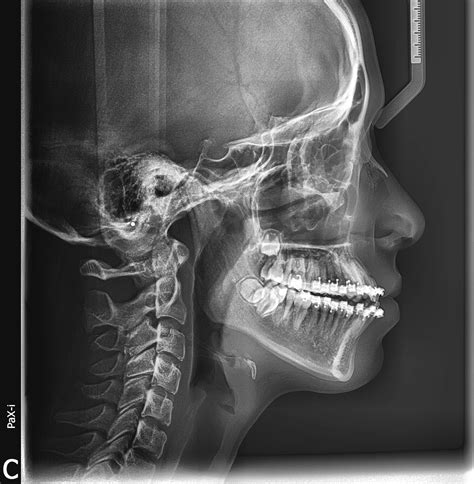

A Cephalometric X Ray is a specialized type of radiograph used to analyze the relationship between the teeth and the jaw. It provides a two-dimensional view of the skull, focusing on the facial bones and teeth. This imaging technique is invaluable for diagnosing and treating various orthodontic conditions, including malocclusions, jaw discrepancies, and facial asymmetries.

The patient’s head is positioned so that the Frankfort plane (a line drawn from the top of the ear canal to the bottom of the eye socket) is parallel to the floor. This ensures that the X-ray beam passes through the skull at the correct angle, providing an accurate image of the facial bones and teeth.

The X-ray machine is then activated, and a beam of radiation is directed through the patient’s head. The radiation passes through the soft tissues and is absorbed by the denser bone structures, creating a detailed image on the X-ray film or digital sensor.

Once the X-ray is taken, the image is developed. In traditional film-based systems, the film is processed in a darkroom. In digital systems, the image is instantly available on a computer screen. The orthodontist then reviews the image to assess the patient’s dental and skeletal structures.